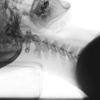

ストレートネックはマッスルインバランスの代表的な上位交差性症候群と言われる状態になりやすいです。上位交差性症候群とは僧帽筋上部や肩甲挙筋など緊張する筋と、僧帽筋下部や頚長筋など抑制される筋が交差している状態です。

これは頭部が前に突き出すことにより、猫背、下部頚椎の屈曲、上部頚椎の伸展が生じています。

頭部の前方突出では、胸鎖乳突筋の過緊張と頚部屈筋群深層の筋力低下が生じていることが多くあります。この場合、胸鎖乳突筋が鎖骨部遠位でより著名となっていることが多いです。

頚部を患者様に屈曲してもらった時に上位頚椎の屈曲が起こらない場合は胸鎖乳突筋の過緊張と環椎後頭関節に関与する筋や靭帯の過緊張が考えられます。